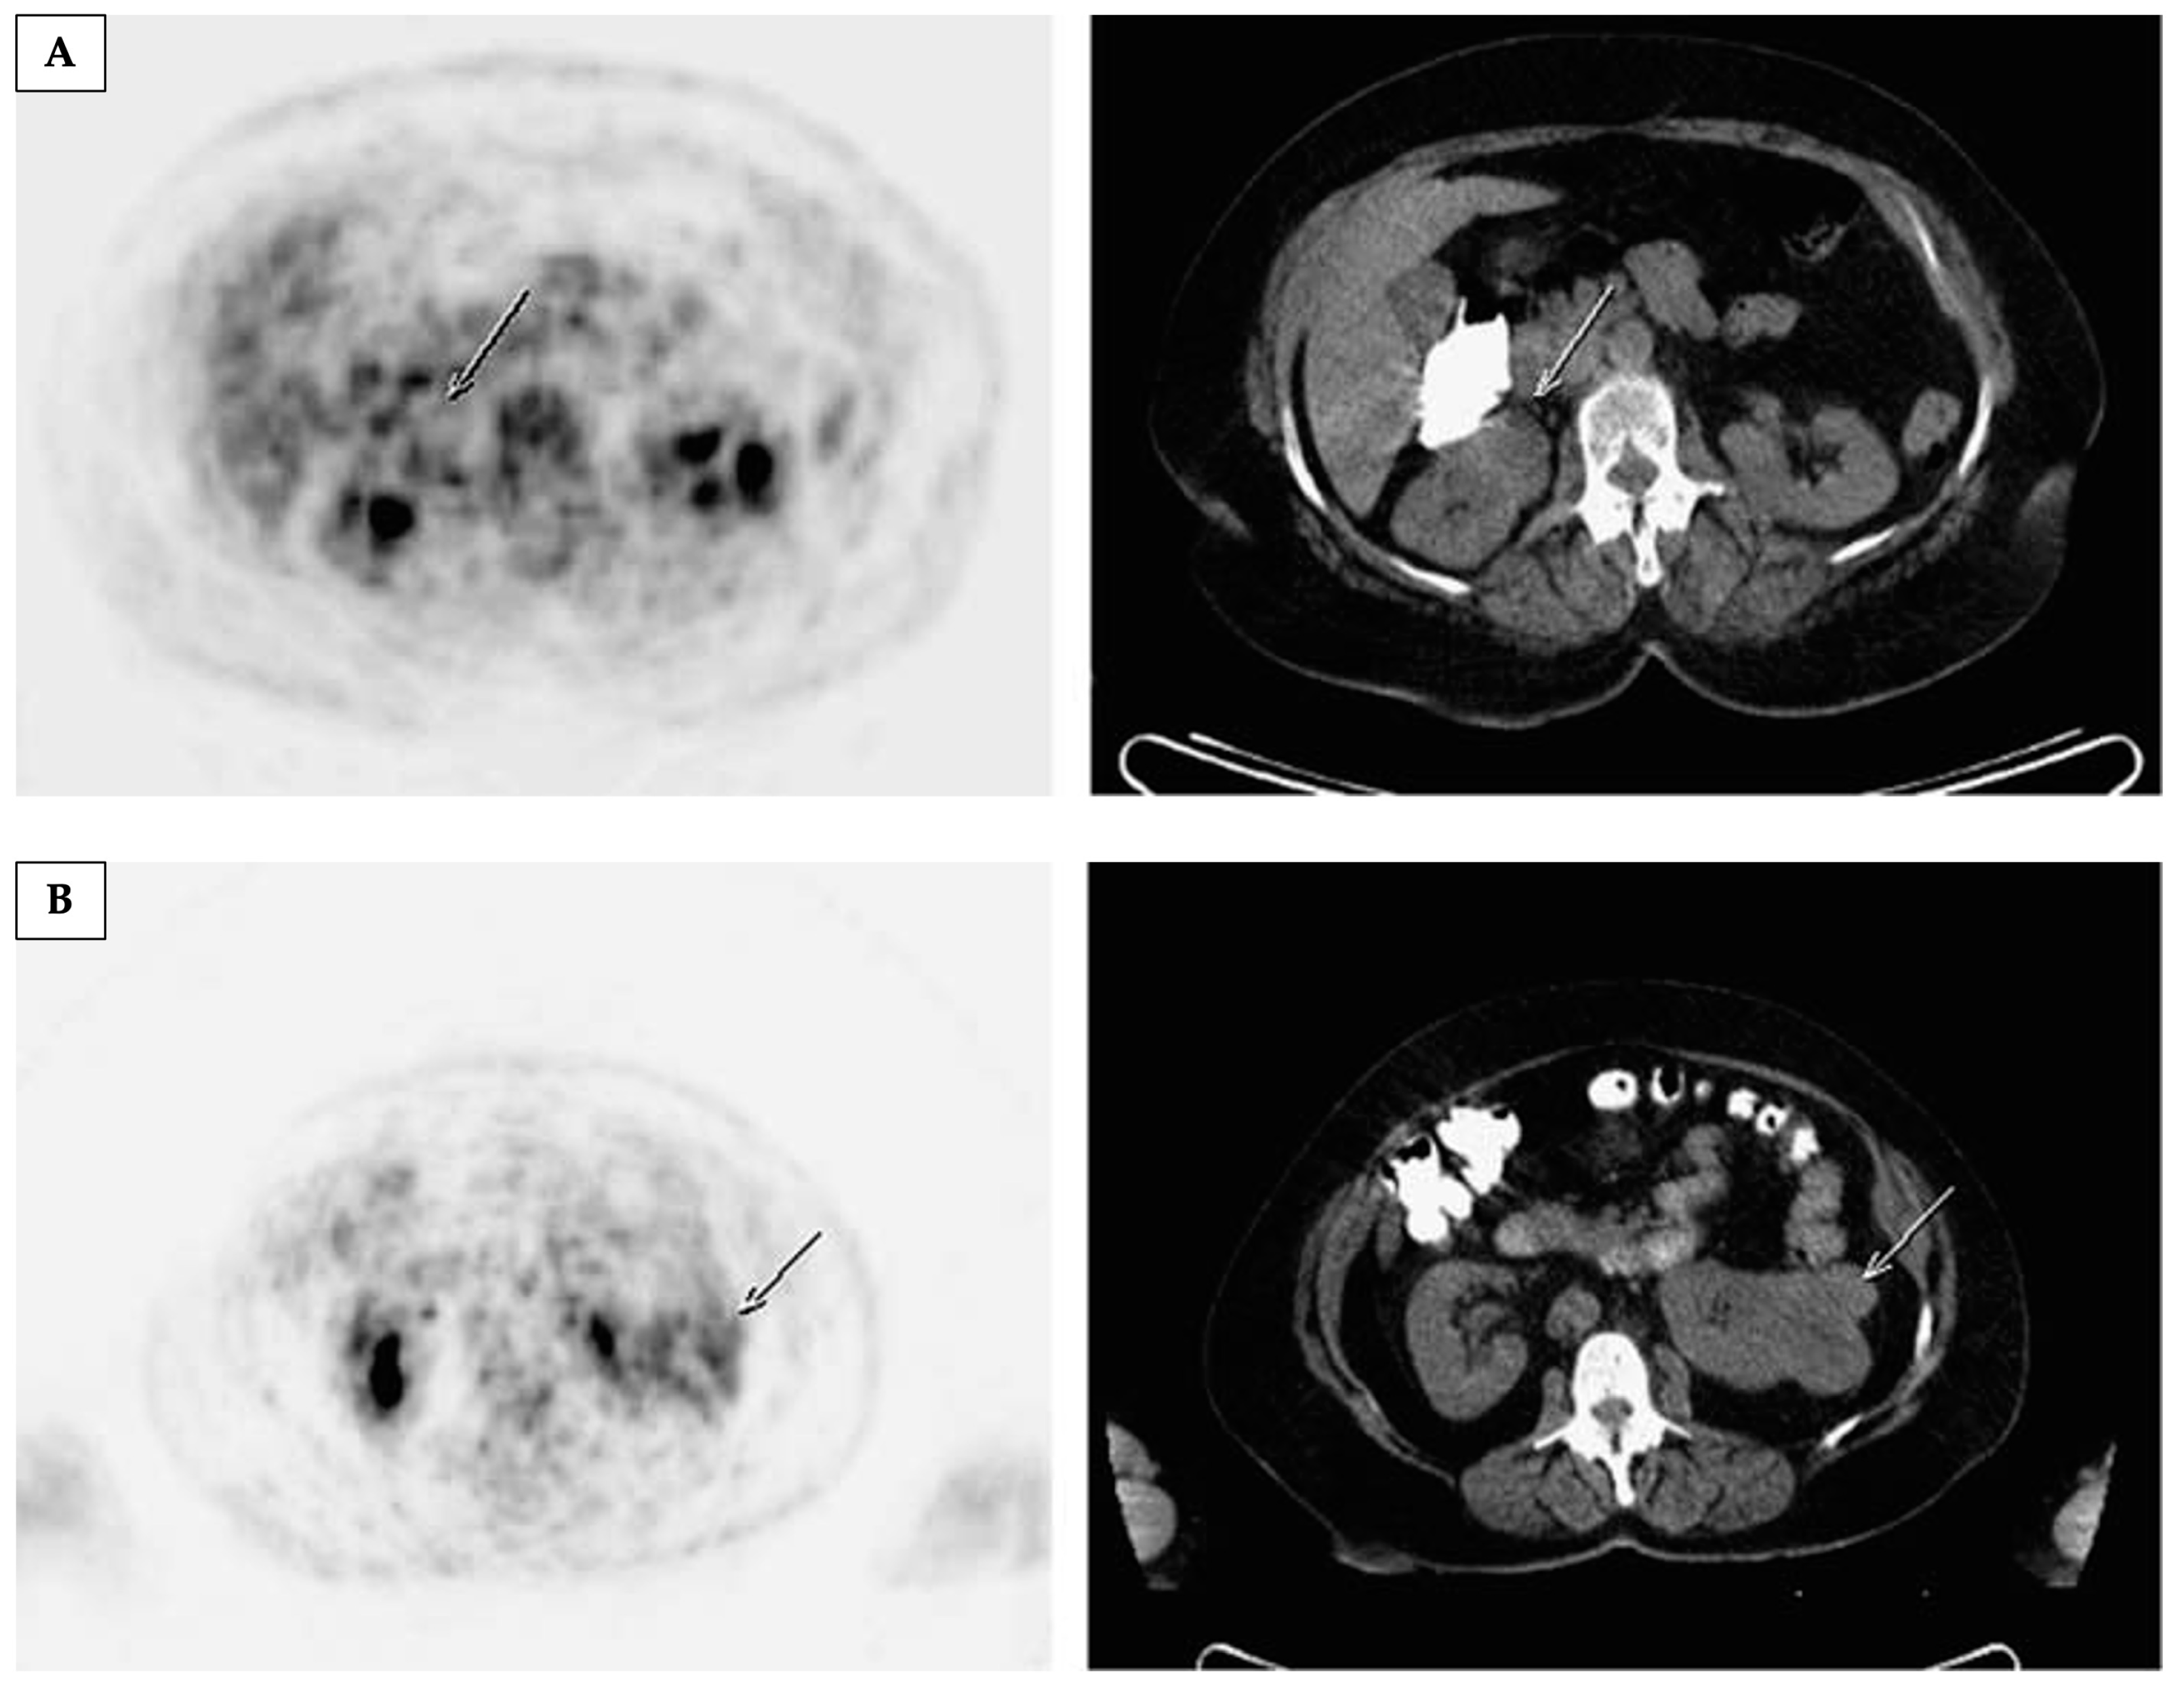

4.1.1. Positron Emission Tomography with [18F]Fluorodeoxyglucose ([18F]FDG-PET)

- Nakajima, R.; Nozaki, S.; Kondo, T.; Nagashima, Y.; Abe, K.; Sakai, S. Evaluation of Renal Cell Carcinoma Histological Subtype and Fuhrman Grade Using 18F-Fluorodeoxyglucose-Positron Emission Tomography/Computed Tomography. Eur. Radiol. 2017, 27, 4866–4873. [Google Scholar] [CrossRef]

- Özülker, T.; Özülker, F.; Özbek, E.; Özpaçaci, T. A Prospective Diagnostic Accuracy Study of F-18 Fluorodeoxyglucose-Positron Emission Tomography/Computed Tomography in the Evaluation of Indeterminate Renal Masses. Nucl. Med. Commun. 2011, 32, 265–272. [Google Scholar] [CrossRef] [PubMed]